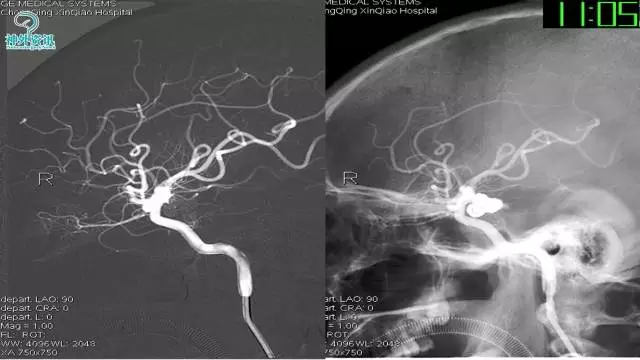

今天为大家分享的是“强生医疗CNV-神经介入专栏”第三十六期,由重庆第三军医大学附属新桥医院神经外科刘俊带来的“Galaxy弹簧圈在不规则动脉瘤中的临床应用”精彩讲课视频及PPT,欢迎观看。文章仅代表作者个人观点,如有不同见解,欢迎同道斧正!